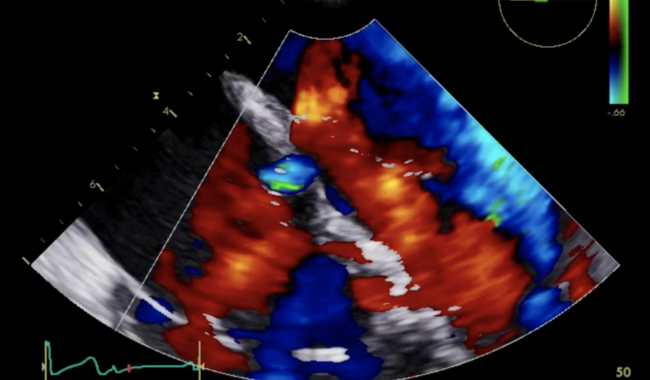

A 52-year-old woman with no known cardiac history developed infective endocarditis of the mitral and tricuspid valves caused by methicillin-sensitive Staphylococcus aureus following skin infection. She demonstrated complete heart block and severe mitral regurgitation (perforation in the anterior leaflet), moderate tricuspid regurgitation with vegetation at the base of the septal leaflet, and a shunt (left-right) from the left ventricle to the right atrium (Figure 1 and Video Series). At surgery, we debrided the mitral and tricuspid valves, and replaced them with tissue prosthetic valves. The inlet of the defect was confirmed to be immediately behind the A2 mitral leaflet. In the right atrium, we identified the shunting defect just in front of the anterior-septum commissure connecting to perimembranous septum (Figure 1). Infective tissue was also observed surrounding the outlet of the defect and was debrided. The defect was closed with autologous pericardium. Postoperative echocardiographic findings were satisfactory without residual shunt flow or perivalvular leak (Video Series). Postoperative recovery was uneventful without infection recurrence. Gerbode defect is a rare complication of infective endocarditis and careful preoperative echocardiographic work-up is imperative for successful repair.